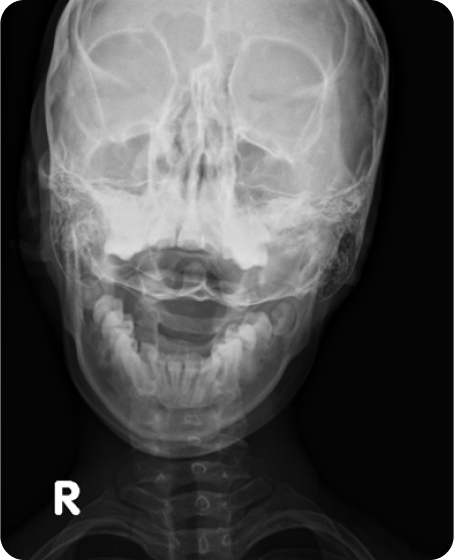

▲ 치료 전 (2016년 1월 21일)

▲ CTA 5개월 착용 (2016년 6월 29일)

▲ CTA 9개월 착용 (2016년 10월 29일)